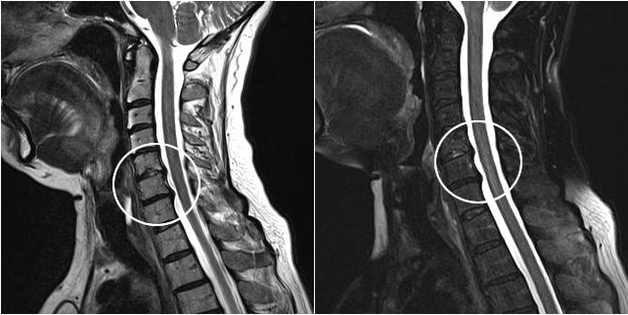

A modern diagnosztikai módszerek közé tartozik az MRI és a CT, amelyek lehetővé teszik a porc- és csontszövet pusztulási folyamatainak legpontosabb vizsgálatát. Ezenkívül ezzel a technikával kényelmes a sérv és más lágyszöveti hibák diagnosztizálása a betegség forrása közelében.